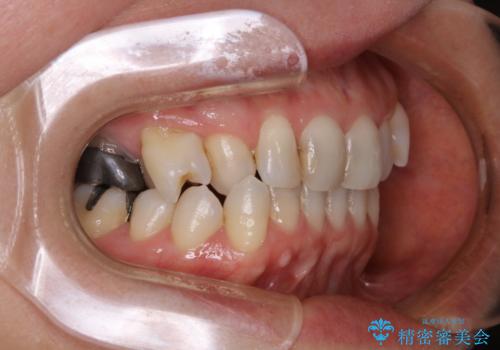

90度捻じれてしまい、完全にはみ出している歯を抜かずにインビザラインで治す。一般治療もできる精密審美会だからこその治療

- 右上の小臼歯が二本とも90度捻じれてしまっており、奥歯の噛み合わせに問題が生じていました。

今回は右上の奥歯に入っていた銀歯の形が悪く、そのせいで歯を並べるスペースが足りない状態でした。

右上の歯の被せ物を作りなおし、適切な歯の大きさに代えてあげることによってスペースを作りました。

また、それだけではスペースが足りない為右上の奥歯は遠心移動を行っています。